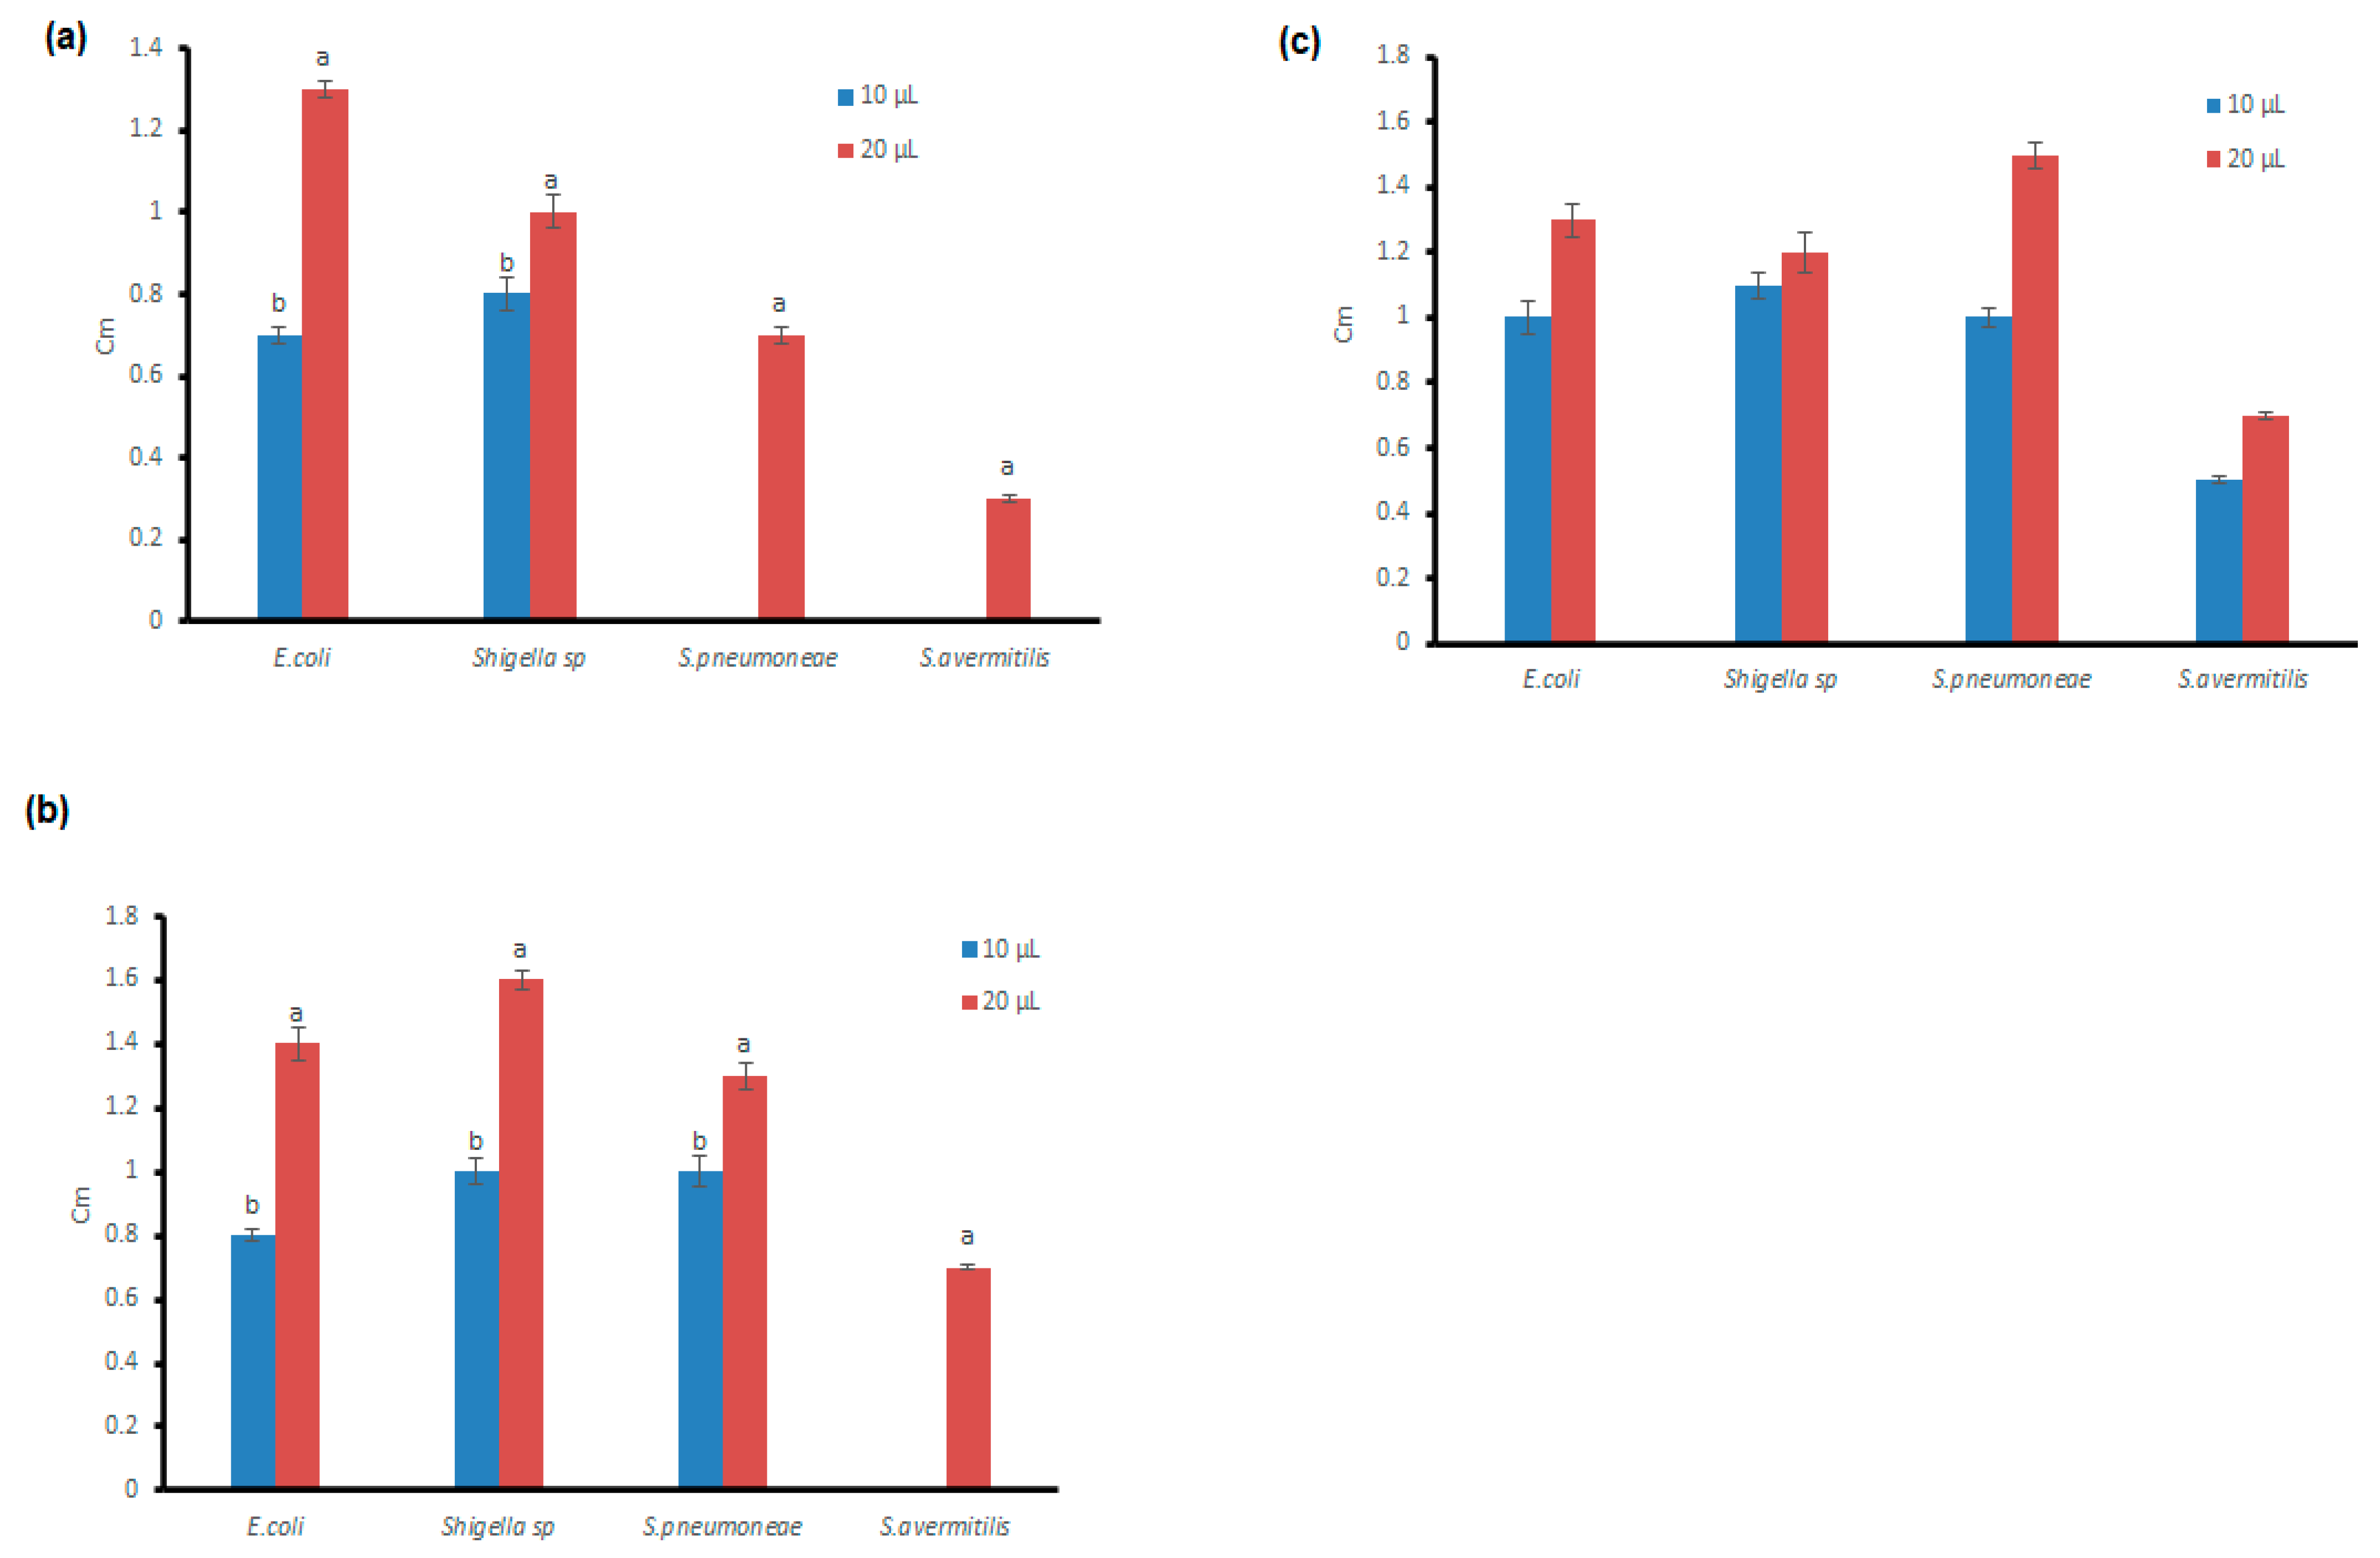

3.4. Antibacterial Potential of the Microfungal Extract